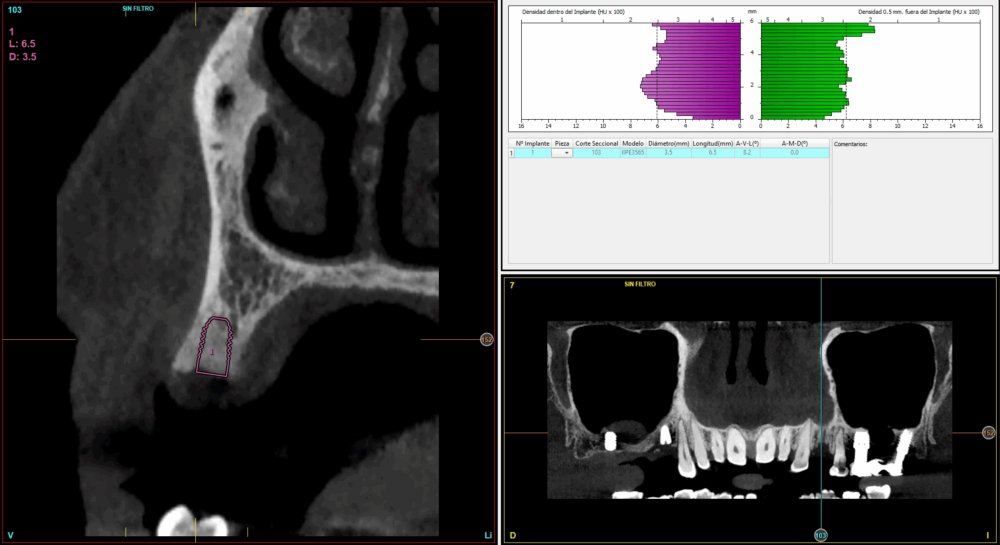

Todas las cirugías fueron realizadas por un único cirujano bajo anestesia local, tras un diagnóstico previo del lecho óseo mediante tomografía volumétrica (CBCT) procesada con un software específico de planificación implantológica (BTI-Scan III). La preparación del lecho implantario se llevó a cabo siguiendo la técnica de fresado biológico a bajas revoluciones descrita por Anitua y cols.19.

Fueron reclutados 21 pacientes en los que se colocaron 21 implantes que reunían los criterios de inclusión anteriormente descritos. Todos los implantes fueron de una longitud de 6,5 mm y el diámetro osciló entre los 3,50 mm el más frecuente con un 66,7% del total, hasta 3 mm en el 14,3%, siendo el restante 19% de diámetro de 3,3 mm. En cuanto a la disposición de los implantes, el 61,8% se situaron en la mandíbula siendo la posición más frecuente en localización de 45 y 46 con un 19% para cada localización. El 38,2% restante se situaron en el maxilar superior, siendo la localización más frecuente en las posiciones de 14 y 15 con un 9,5% cada una de ellas. El resto de las localizaciones se muestran en la Figura 1. El tipo óseo de los implantes insertados fue tipo II en el 66,7% de los casos, de tipo III en el 23,8% y de tipo I en el 9,5%. Si lo distribuimos por regiones anatómicas el más frecuente para el maxilar fue el tipo II (60%) y para la mandíbula también (54,5%). La distribución de los tipos óseos en función de la región se muestra en la Figura 2. El torque medio de inserción de los implantes fue de 37,14 Ncm (+/- 14,54). Los torques en función del tipo óseo y la localización anatómica se muestran en las Figuras 3 y 4. En 11 de los pacientes se llevó a cabo una carga inmediata, y en el resto una diferida.

En cuanto a la rehabilitación protésica, en todos los casos se utilizó una prótesis atornillada con transepitelial para prótesis unitaria. La supervivencia de las prótesis fue del 100%, sin encontrarse fracaso en ninguna de ellas al igual que los implantes, con un tiempo de seguimiento de tres años. Durante el primer año, en las visitas de control, ninguno de los implantes mostró sangrado al sondaje ni inflamación de los tejidos periimplantarios. La media de la pérdida ósea en este punto fue de 0,32 mm (+/- 0,60) y la media de la pérdida ósea distal de 0,31 (+/- 0,48). A los dos años, no se registraron tampoco signos inflamatorios en ninguno de los implantes y la pérdida ósea mesial del conjunto fue de media de 0,38 mm (+- 0,54) y la distal de 0,64 mm (+/- 0,70). En la última visita a los 3 años, los tejidos periimplantarios siguieron estables, sin signos de inflamación y la media de la pérdida ósea mesial fue de 0,40 mm (+/- 0,53) y la distal de 0,69 (+/- 0,55) (Figura 5). En las Figuras 6-12 se muestra uno de los casos incluidos en el estudio.